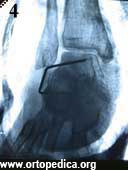

4. Рентгенограмма после операции подтаранного артродеза

Рентгенограмма в боковой проекции после операции подтаранного артродеза Рентгенограмма после операции подтаранного артродеза Рентгенограмма через 2 месяца после операции подтаранного артродеза